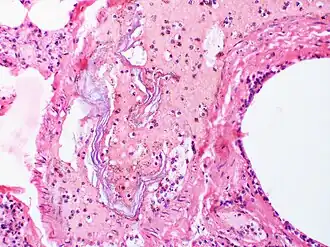

Эмболия околоплодными водами — осложнение при бурной родовой деятельности, предлежании плаценты, преждевременной отслойке нормально расположенной плаценты, связанное с попаданием амниотической жидкости в лёгочный кровоток матери.